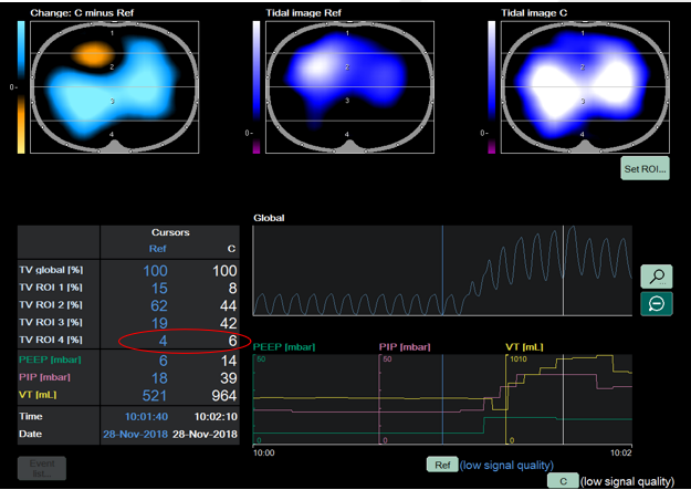

EIT技术能够在自主呼吸试验(SBT)期间,对潮气量的空间分布进行可视化呈现与定量化分析。GI升高或EELV下降(提示肺塌陷发生)时,可作为预测SBT失败的指标。如图3所示,在实施肺复张操作前后,肺部通气状况呈现出显著差异,借助EIT可清晰捕捉并直观展现这种变化,为评估肺复张效果、指导呼吸治疗提供有力依据。

图片

3  肺复张前后肺部通气的分布情况

评估肺的可复张性,可通过对比两个不同时间点潮气图像的阻抗差值实现。将差值以图像形式呈现(差值图像)4,能够精准判别肺内通气阻抗变化的部位,明确是哪些区域的阻抗增加(提示通气改善等可能),又或是哪些区域的阻抗减少(可能存在肺塌陷等情况),从而为判断肺复张效果、分析肺通气功能状态提供直观依据。

4  阻抗差值图像

肺可复张性评估参考流程如下:①设置ROI:采用分层模式,将肺部分为腹侧与背侧区域;②实施肺复张并对比分析:在实施肺复张操作后,对比复张前与复张过程中的肺通气分布状态,核心评估指标为通气分布的均一性是否改善;③判定可复张患者:对于背侧区域(ROI 4)的通气量较复张前出现明显增加的患者,可判定为具备可复张性的患者。图5-7所示为经EIT评估的肺可复张性。

5  有可复张性

6  部分可复张性

7  无可复张性